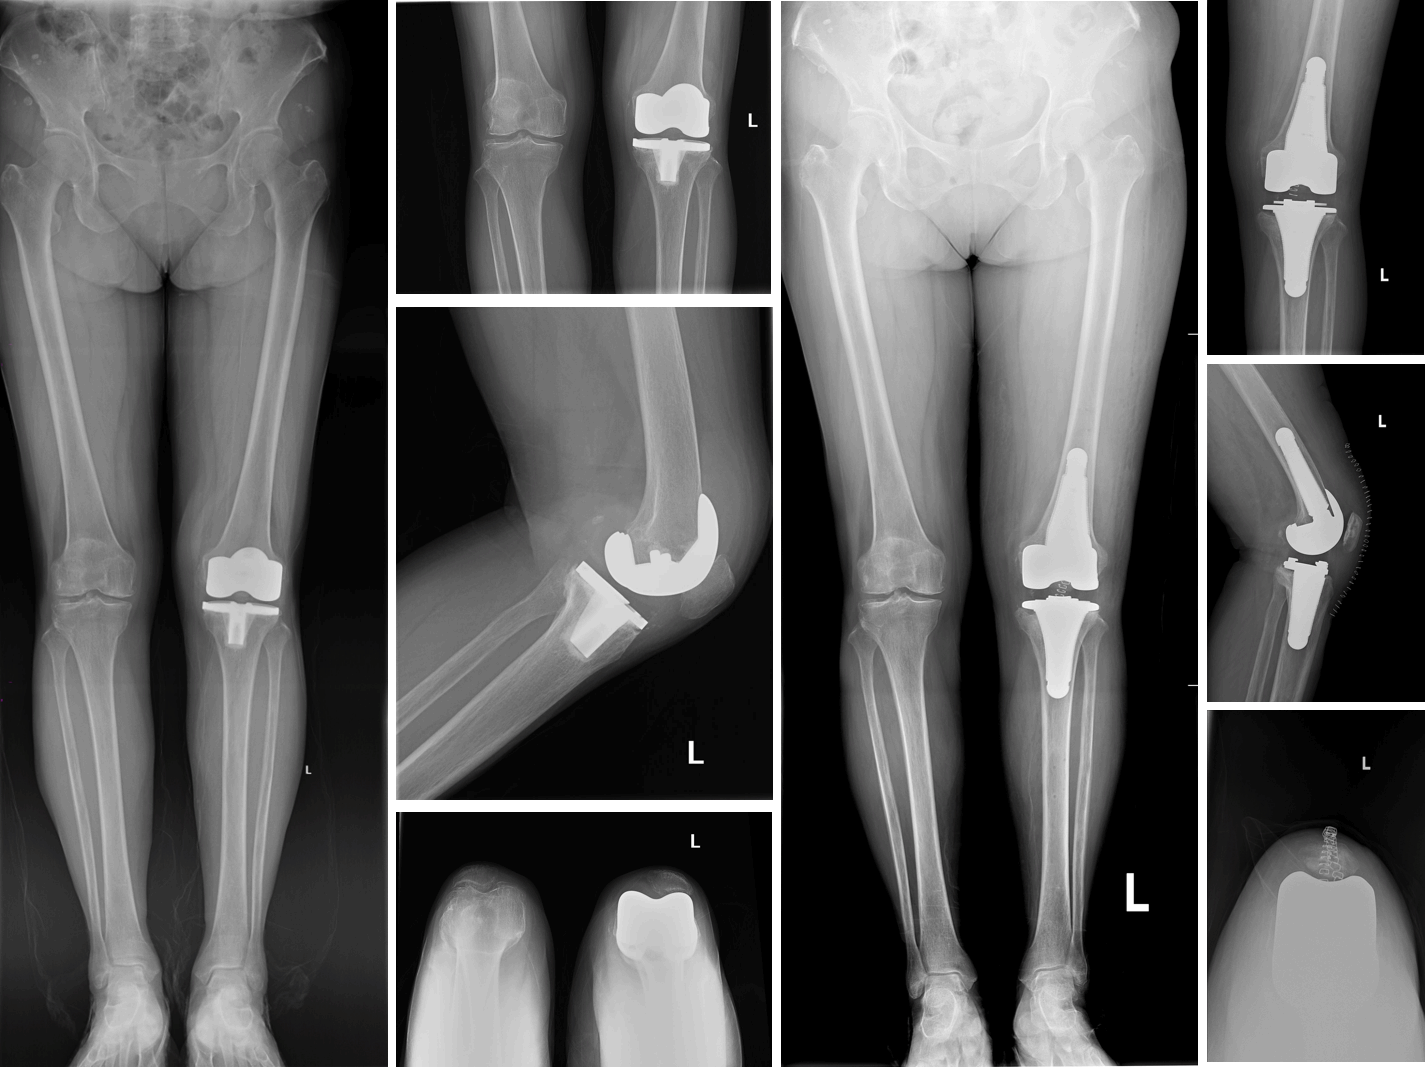

术前影像与术后影像

患者是一位73岁的女性,6年前因膝骨关节炎于当地医院行左膝关节置换术,之后因为膝关节置换术后无菌性松动,左膝关节已经疼痛1年余。该手术使用的3D打印生物型膝关节置换翻修假体系统,融合了3D打印钴铬钼合金和3D打印钛合金等金属增材制造技术,根据患者影像学数据进行了个性化定制,确保在干骺端区域有良好的稳定性,且操作简单。该系统实现了生物型固定(髌骨假体除外),具有良好的骨长入性能和远期稳定性。